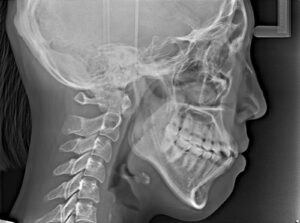

レントゲン・必要に応じてCT

顔貌(横顔)のバランス評価

そのためレントゲン撮影でセファログラム(cephalogram 頭部X線規格写真)を撮影する必要があります。